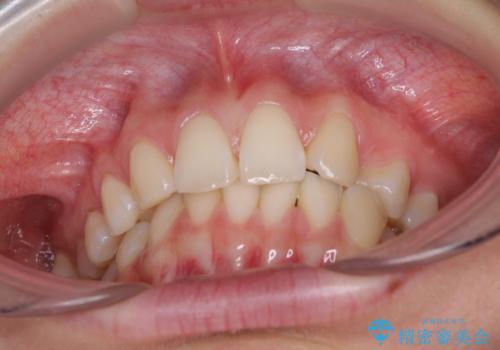

上顎前歯が2本欠損 インビザラインによる叢生の解消

- 深い咬み合わせと前歯のデコボコを気にして来院された患者様です。

上顎前歯2本が欠損しているため、妥協的なゴールを設定しインビザラインで矯正治療を行うこととしました。

上下前歯の大きさのアンバランスにより、深い咬み合わせと奥歯の咬みにくさがなかなか解決されず、治療に長期間を要することとなりました。